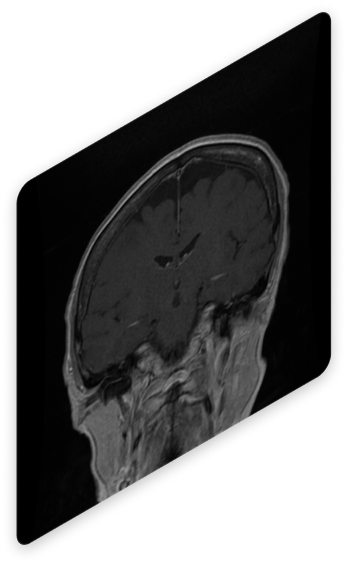

Visualización de las Adquisiciones

Revisa las imágenes adquiridas desde un visor profesional

El simulador incluye un visor integrado que permite interactuar con las imágenes, explorar cortes anatómicos y obtener una comprensión detallada de los resultados.